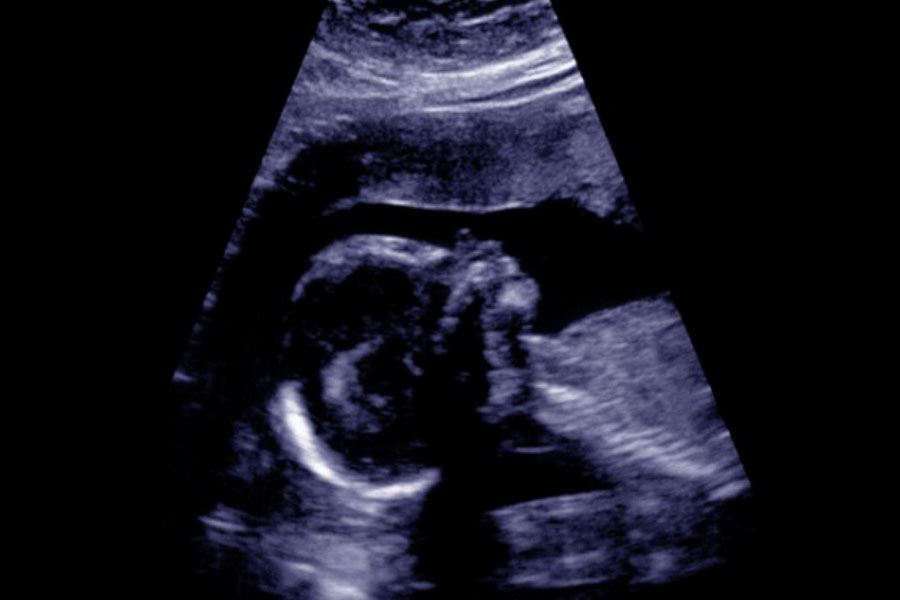

Please take a look at the photo for more information about making decisions about your care.